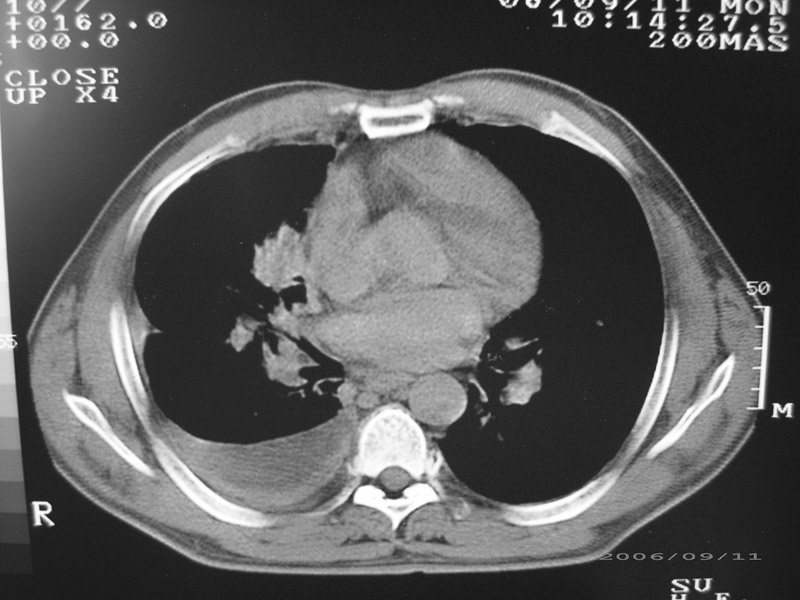

以下是引用守望可可西里在2006-9-11 15:29:00的发言:[br][br] ct平扫表现:右侧胸膜腔缩小,积液,胸膜增厚且不均匀、不规则,以纵隔胸膜增厚为主,边缘呈锯齿状,并见附壁内突之结节状肿块影。右肺含气量减少,纹理聚集,右肺门中下部见数个肿大的淋巴结。纵隔无移位,内未见明显肿大淋巴结,双侧主支气管以及各叶、段支气管比较通畅。。[br] 考虑:右侧胸膜恶性间皮瘤,伴肺门淋巴结转移。